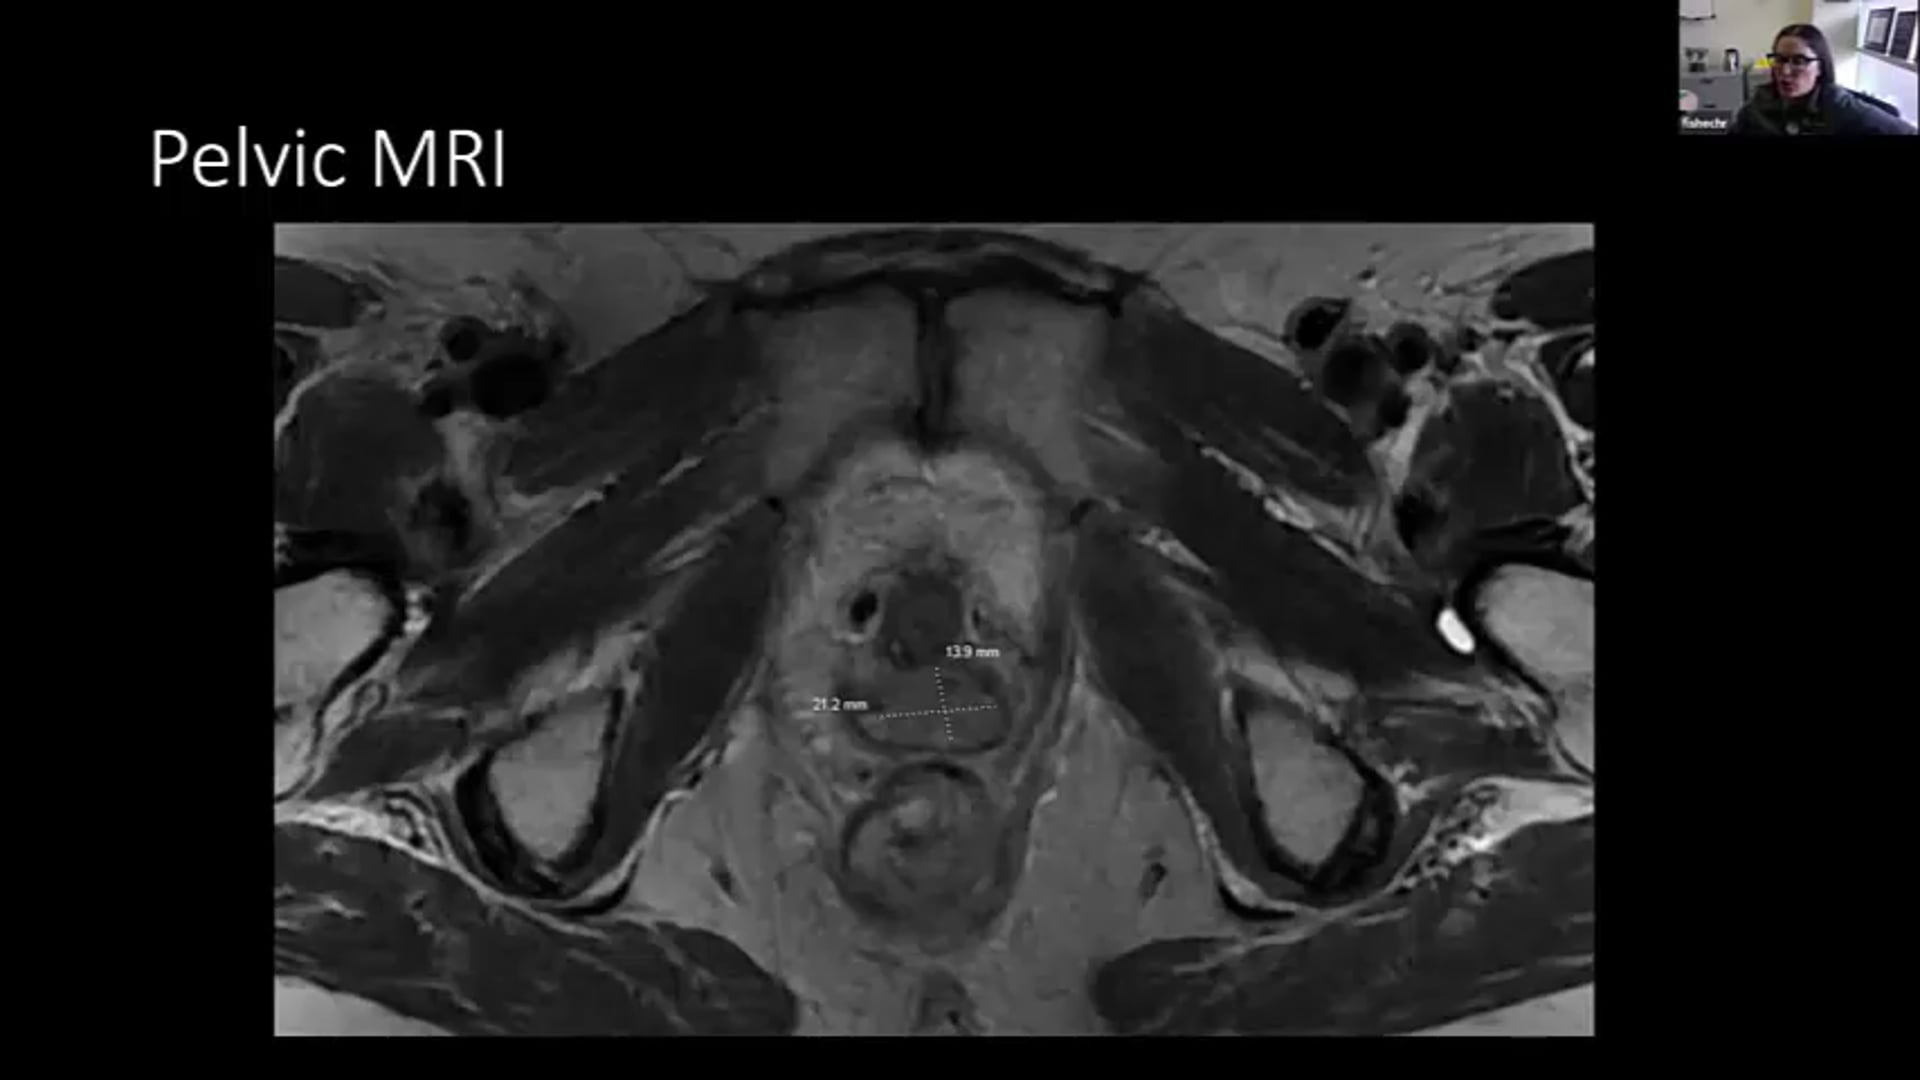

01/14/21 - Dr. Jessica Huang - Radiation Oncology - GYN Brachytherapy

MRI-Guided GYN Brachytherapy, MRI with applicator, MRI scheduling, Dose constraints, carcinoma in the cervix,